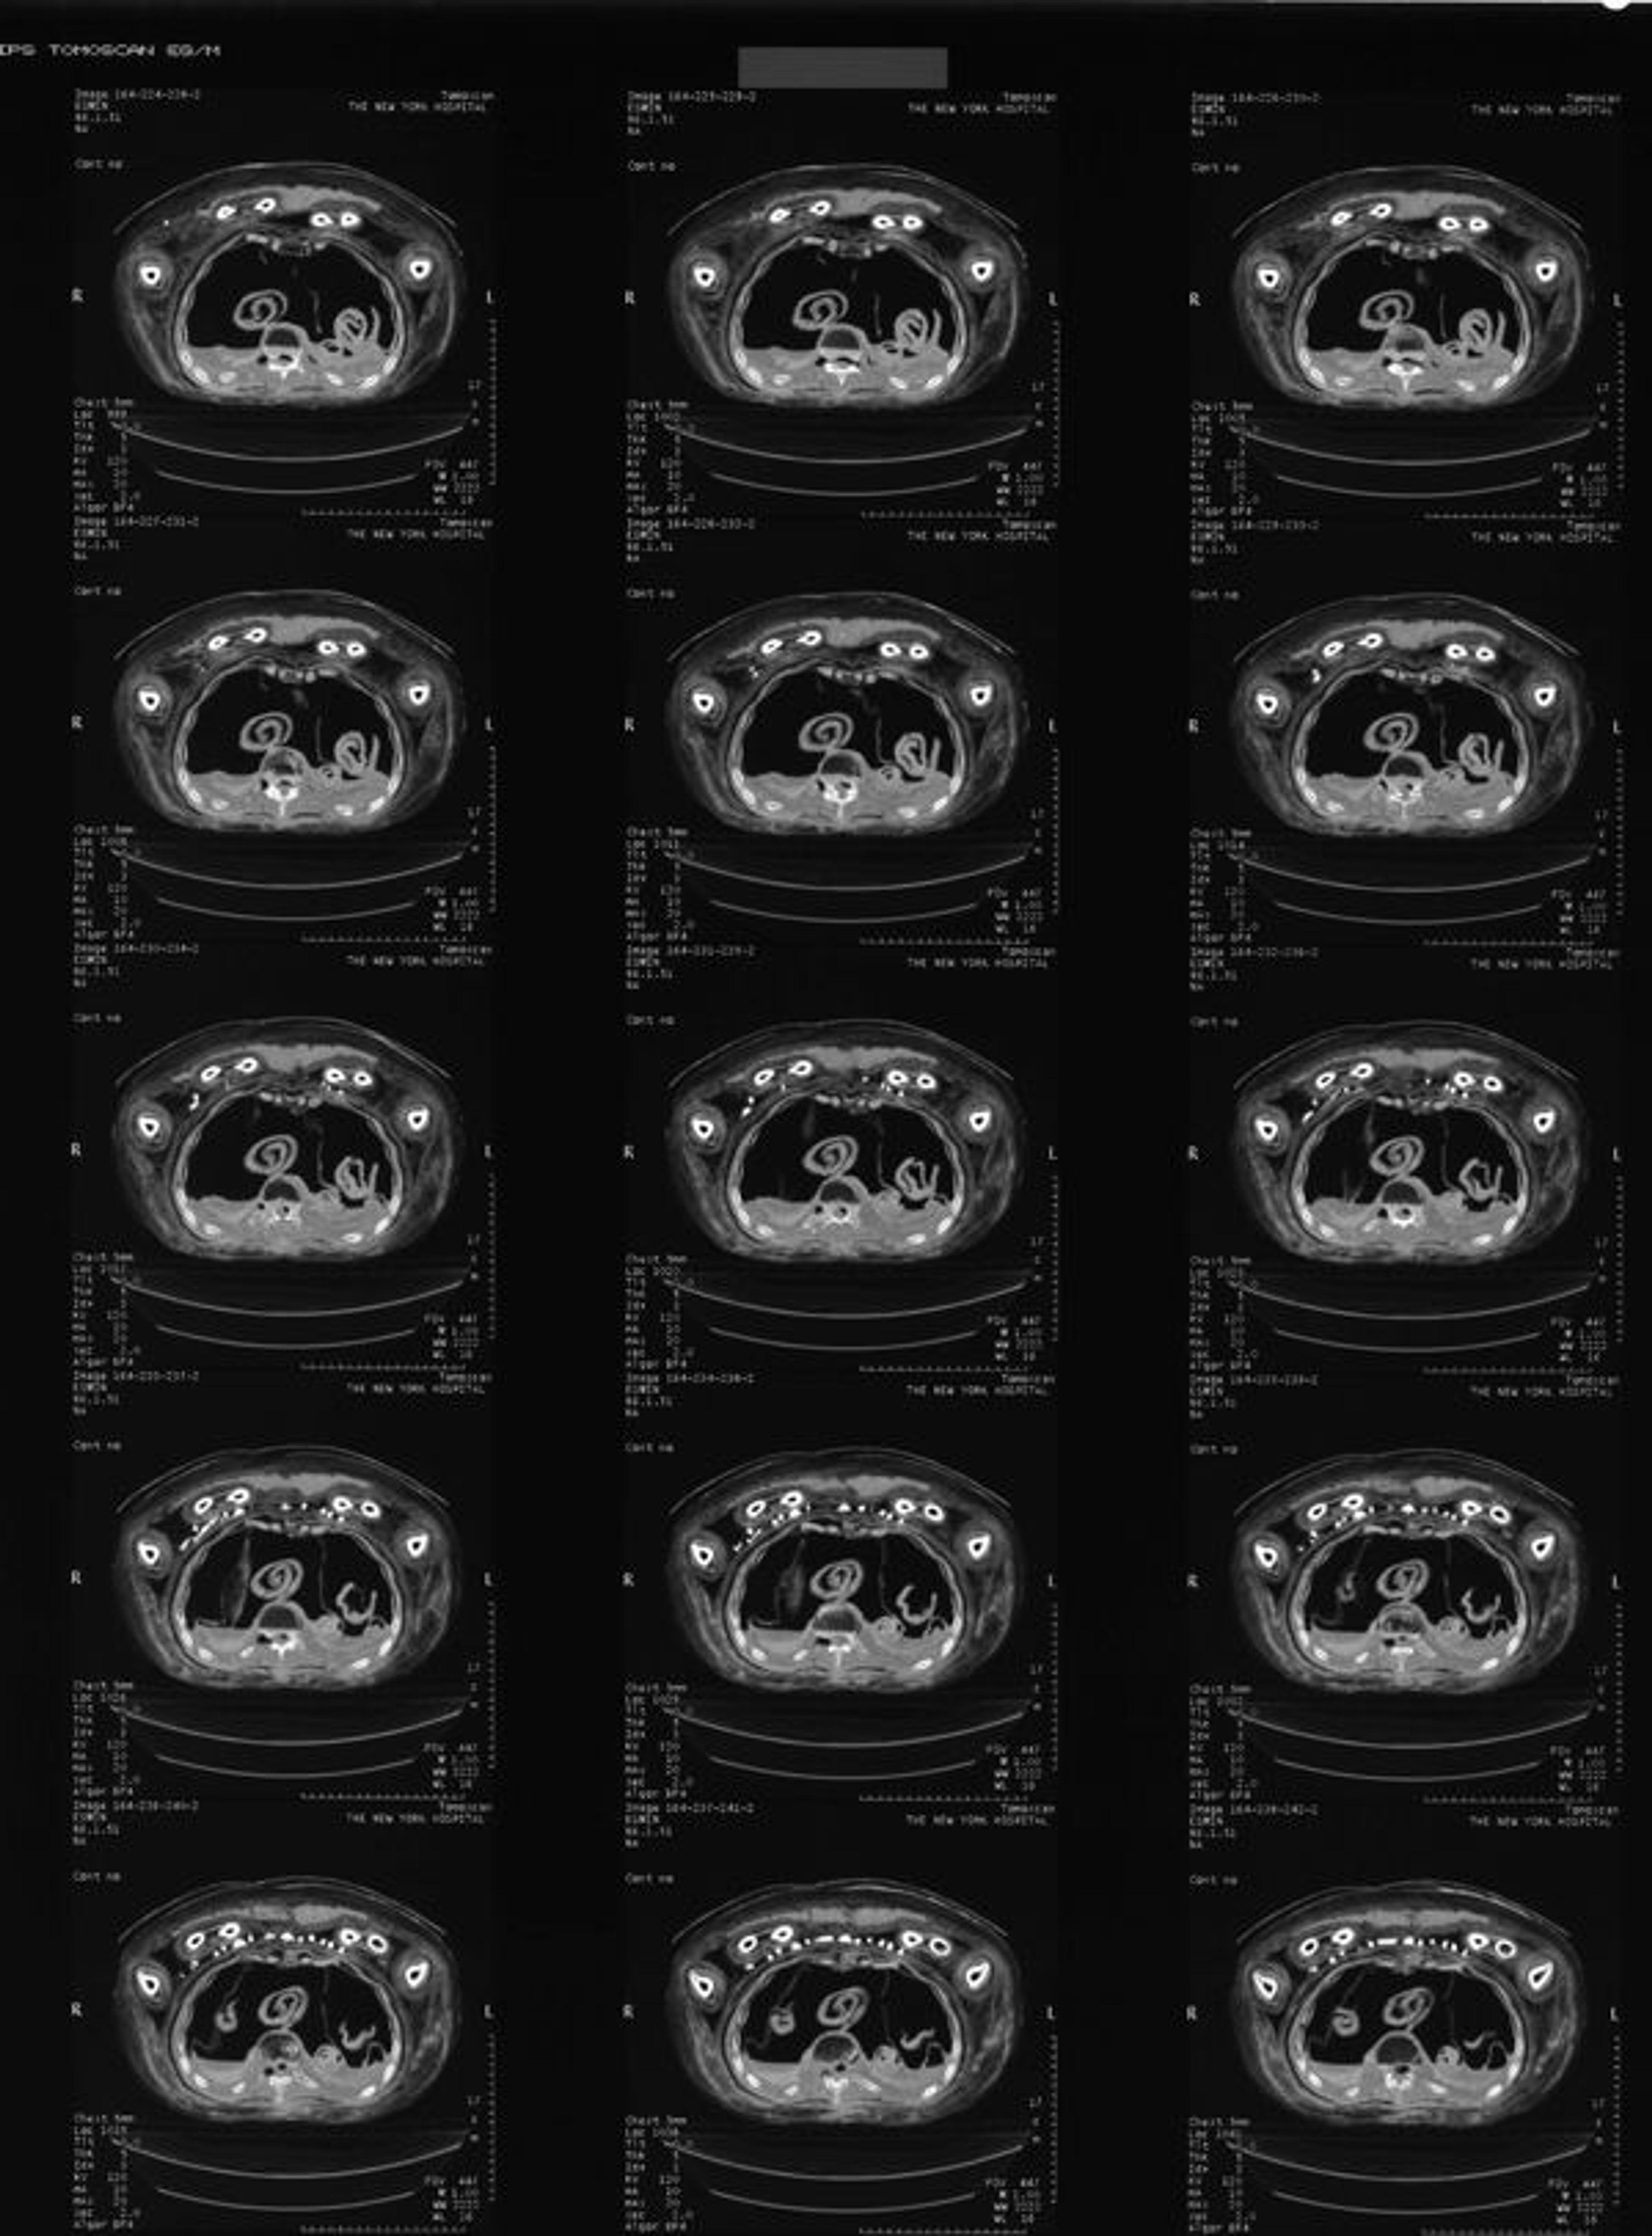

Fig. 7. Example of old film sheet with CT scan images from 1997.

Older X-rays and CT scans of Nesmin that were taken in 1995 and 1997 (figs. 7–8, 10, and 13)2 had shown that his mummy is accompanied by a very large set of amulets (thirty-one in total) within the wrappings. The images that were produced at the time were on film and allowed the identification of the types of amulets (such as a standing god), but the information from these old images was limited and the visible details were not sufficient to permit the identification of the particular gods included, for example.